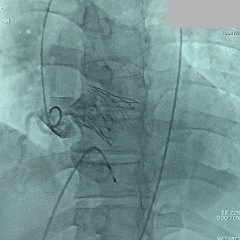

术中影像

根部造影:可见大量反流

导丝跨瓣

预弯型系统顺利跨过横位心

平齐窦底猪尾,0位定位

展开后造影,瓣膜位置偏深

回收后再次释放

第二次展开造影,瓣膜位置尚可,基本无漏

多角度评估,瓣膜深度可

脱钩释放

脱钩后,瓣膜无位移

造影评估,瓣膜深度可,无瓣周漏

左头观察,腰征明显,锚定稳定